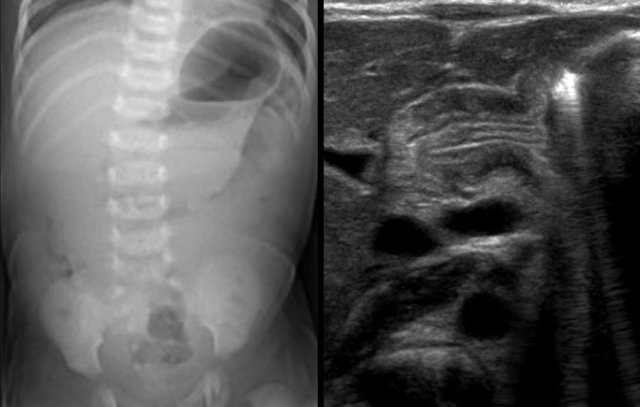

Here another typical case of NEC.

Notice the air in the portal vein (arrow) and peripheral portal branches.

This is seen on the X-Ray and on ultrasound.